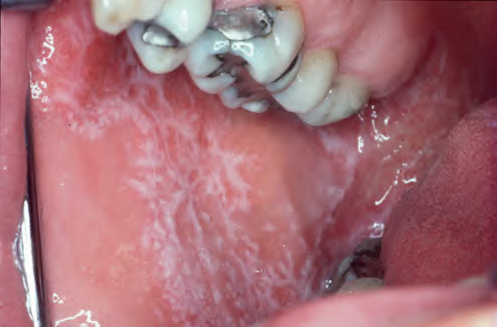

口腔扁平苔藓可发生于口腔黏膜的任何部位,常多个部位同时发生,以颊部最为常见,其次为舌、唇、牙龈、腭部等,大多左右对称。

主要表现为小疹子连成的线状白色、灰白色花纹,看起来确实有点像苔藓,但其实只是病损的一种表现形式。

▲ 口腔扁平苔藓典型表现